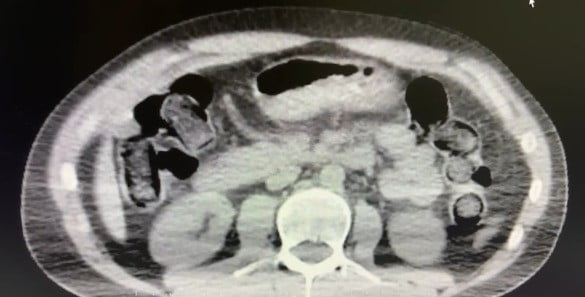

Ekiplerin sokak satıcılarına yönelik çalışmalarını yoğunlaştırması sonucu, şüpheliler S.B. ve O.R.'nin "yutma yöntemi" ile kente uyuşturucu madde sevk edeceği bilgisi üzerine operasyon düzenlendi. Şüphelilerin ikametlerinde ve araçlarında aramalar yapıldı.

Aramalarda; 101 kapsül halinde 722 gram uyuşturucu madde, 1 adet hassas terazi, yutma yönteminde kullanılan muhtelif materyaller ile uyuşturucu ticaretinden elde edildiği belirtilen 20 bin 210 TL, bin 320 euro ve 10 ABD doları ele geçirildi.